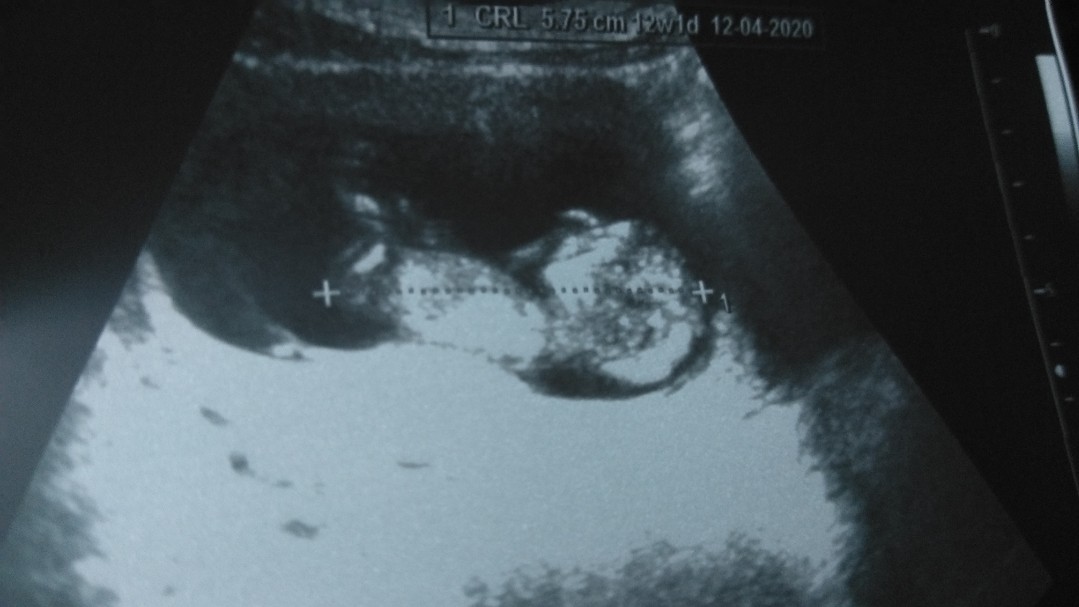

กำหนดคลอดซาวตอน7 wหมอให้กำหนดคลอด8/3/63 ภาพนี้ซาวประมาณ18w หมอให้กำหนดคลอดใหม่3/3/63 ปัจจุบันตอนนี้20w จ้าน้องเป็นผู้หญิง